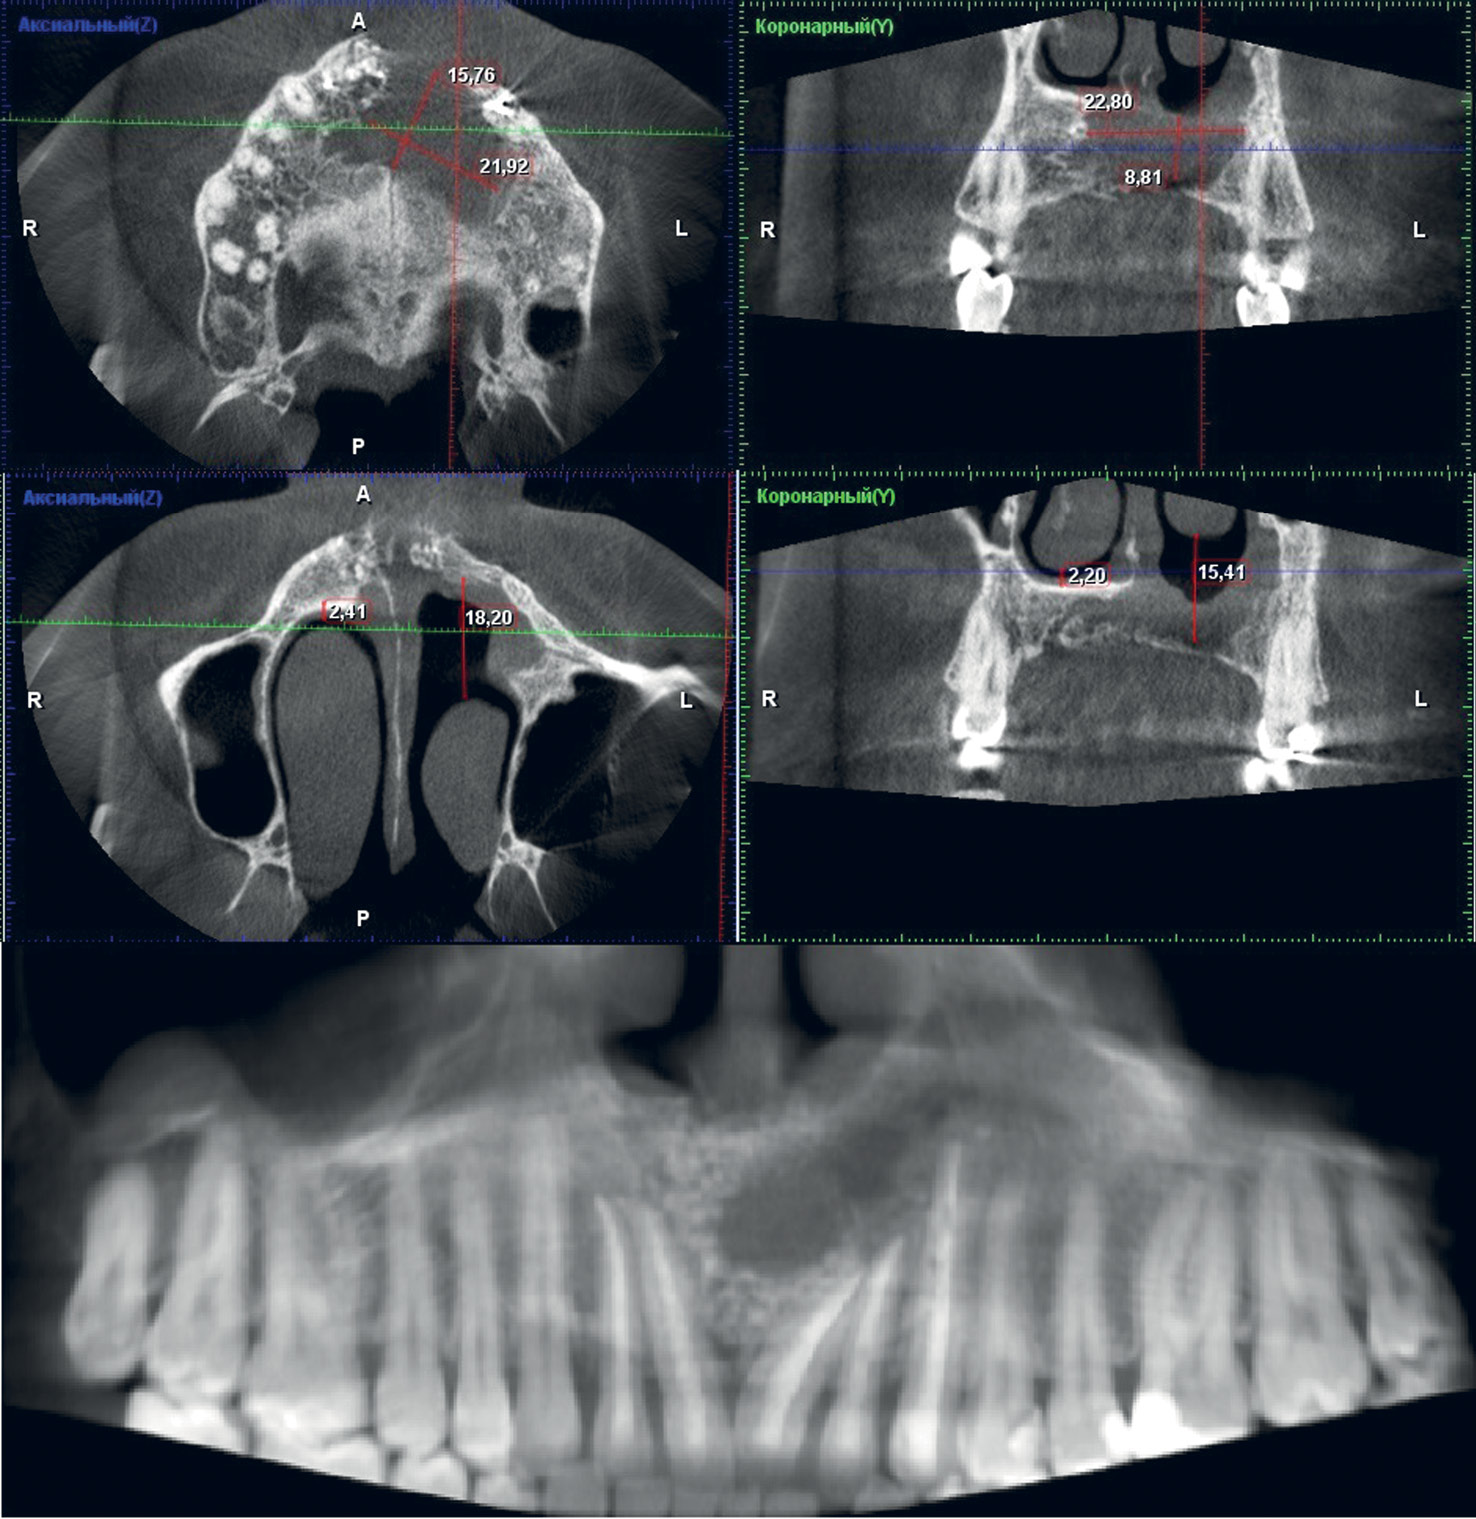

На конусно-лучевой компьютерной томограмме определяется очаг деструкции костной ткани округлой формы с четко ограниченными контурами, размерами 45,46×22,5×39,7 мм (рис. 1). Сверхкомплектный зуб располагается в полости очага деструкции верхней челюсти, частично оттесняя передненижнюю стенку левого верхнечелюстного синуса и нижнюю носовую раковину на 12 мм относительно нижней носовой раковины с противоположной стороны.

Рис. 1. Пациент Д., 33 года: данные конусно-лучевой компьютерной томографии на первичном приеме